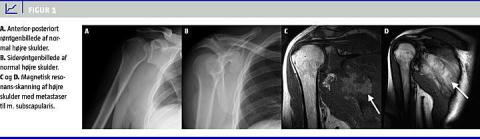

Røntgenbillederne viste ikke nogen fraktur eller luksation (Figur 1 A, B). Manden blev derefter set i ortopædkirurgisk ambulatorium af en speciallæge. Smerterne gav indtryk af supraspinatus tendinitis og rotator cuff -syndrom. Blokader, der blev givet subakromielt og intraartikulært, lindrede kun kortvarigt. For at afklare, hvorfra smerterne stammede, blev der ordineret magnetisk resonans-skanning, obs. impingement . Skanningen viste en lobulær tumor, der involverede både m. subscapularis dxt. og m. infraspinatus dxt. med osteolytisk destruktion af scapulae (Figur 1C, D).